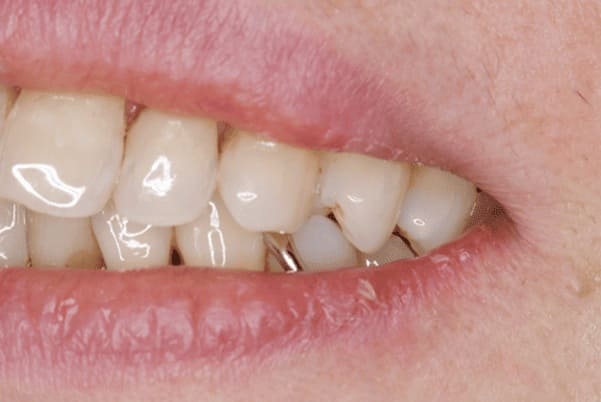

上あごに接する入れ歯に違和感がありになっていたとのことで、プラスチックが大きく削られた入れ歯をされていました。

そのため入れ歯の安定が悪く、お食事の際に入れ歯が動き、がたつきを感じられている状態でした。

前歯にバネにより見た目の問題も抱えておられました。

かみ合わせが低くなった歯を本来の高さに戻し、保険では使用できない歯に負担のかかりずらいバネで、歯の保存、審美性を確保しました。

前歯にバネを設定せず、見えない奥歯に維持力をもたせたバネを用い、またバネのかかる歯の負担軽減を目的に、被せ物は繋げることで強度を増す設計とすることで、入れ歯が動かずガタつき、審美性不良が解消されました。

入れ歯を修理する中で、入れ歯の上あごの接触面積ではなく、厚みに対しての違和感と診断し、薄い金属を用いた従来の厚みを1/3程度にした入れ歯にすることにより違和感は消失しました。